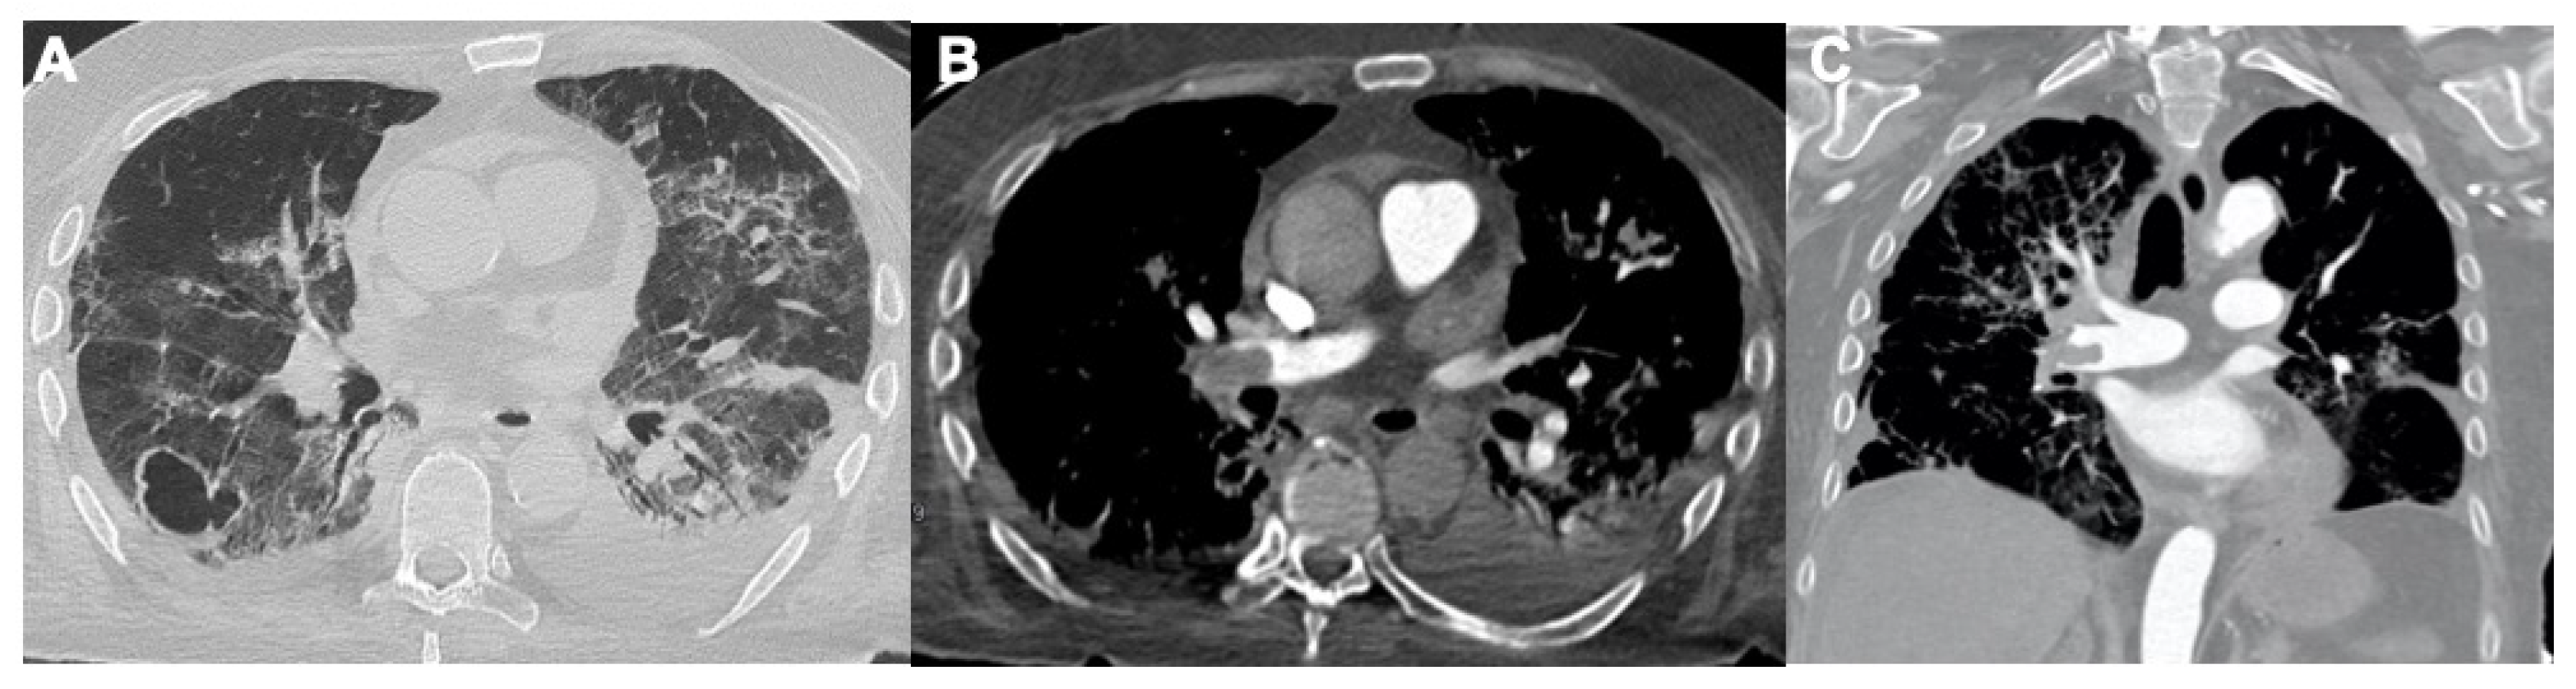

2.3. Pulmonary Embolism